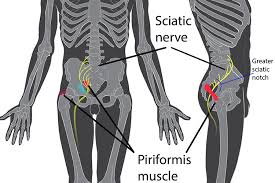

Download Sciatic nerve pain pictures